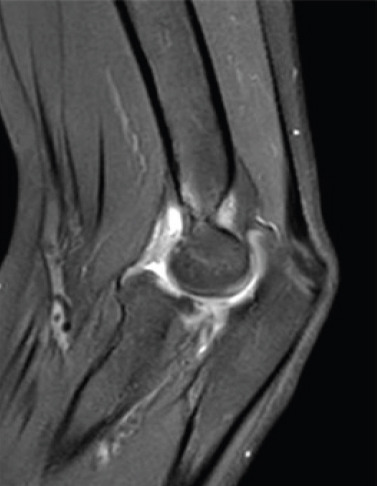

Introduction: Association of elbow dislocation, radial neck fracture (RNF), and ulnar shaft fracture has not been reported previously in the pediatric population.

Case report: This 11-year-old girl fell from her height. She presented a severely displaced RNF, a greenstick fracture of the proximal ulnar shaft, and a posterior elbow dislocation.

Conclusion: This article describes a very rare case, shows a possible treatment, and presents the follow-up with a final good result.